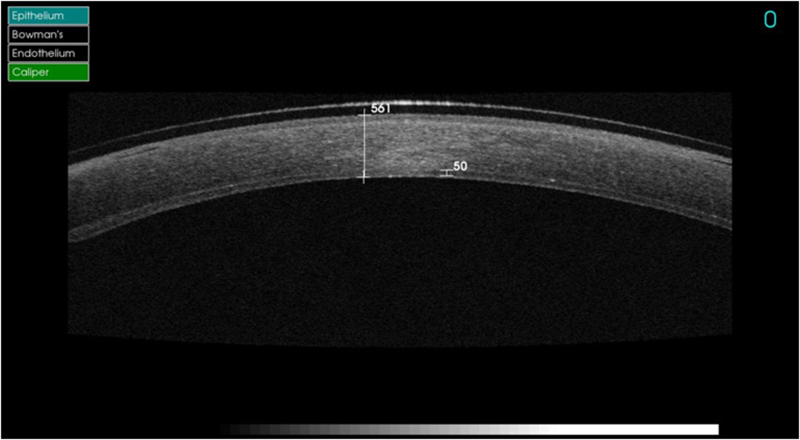

En los casos de pacientes con disfunción endotelial se realiza una DSAEK/DSEK o DMEK. La mayoría de estos pacientes están afectados por distrofias endoteliales, mayormente la distrofia de Fuchs, también traumatismos corneales, fallo de un injerto y la queratopatía bullosa. En la DSEKse realiza la técnica manualmente y se obtiene un lecho de estroma-MD-endotelio que puede variar de espesor en función de la profundidad. Vemos un ejemplo en la

Figura 9, donde observamos un lecho de 50 micras de espesor, con un total de 561 micras. Un resultado más que óptimo. En otros casos puede ser dificultoso obtener el lecho lo más fino posible como es el caso de la

Figura 9. DSEK con injerto de 50 m.